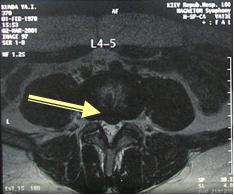

Единственно информативным методом в диагностике грыжи МПД на поясничном уровне является магнитно-резонансная томография (МРТ). Спиральная компьютерная томография (СКТ) имеет гораздо меньшую информативность в диагностике грыж МПД. !!! Хирургическая тактика в лечении межпозвоночных грыж планируется только на основании данных МРТ.